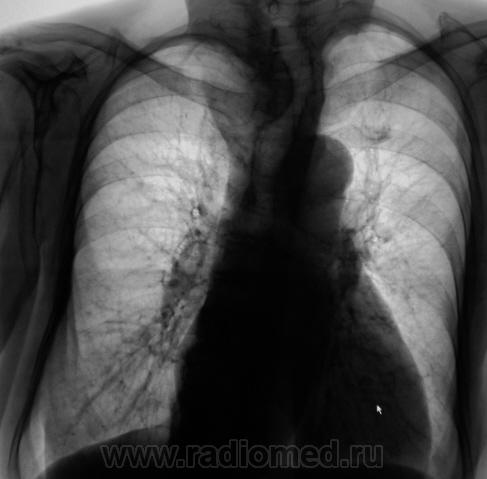

Экспансивно растущее об"емное образование верхнего средостения, неоднородной структуры за счет включений кальция. Состоит ли на учете у эндокринолога? Похоже на "ныряющий" зоб.

На учете не состоит. О патологическом процессе ранее было ничего не известно. "Выцепили" сегодня, сегодня и дообследовали.

Думаю, что не "ныряющий", а конкретно "нырнувший", да там и "заночевавший" загрудинный зоб, включения кальция ничего хорошего не сулят. Согласен - УЗИ с, при необходимости,  биопсией.